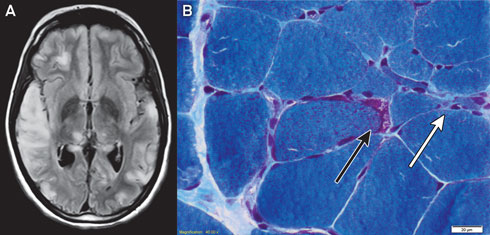

Magnetic resonance imaging of the patient’s brain demonstrated increased T2 signal involving grey and white matter throughout both cerebral hemispheres, most confluent in the right temporal and parietal lobes (Box 1, A). An electroencephalogram displayed a slow rhythm with epileptic activity in the temporal and centroparietal regions.

Histological examination of a biopsy of the gastrocnemius muscle was consistent with MELAS syndrome (Box 1, B). Electron microscopy of a muscle biopsy sample revealed mitochondria with abnormally arranged cristae and abnormal electron densities. Mitochondrial respiratory chain enzyme studies on muscle samples were within normal limits, but the common m.3243A>G mutation in the MTTL1 gene was detected in about 70% of the mitochondrial DNA (mtDNA) in muscle tissue and in 10% of the mtDNA of the peripheral blood.